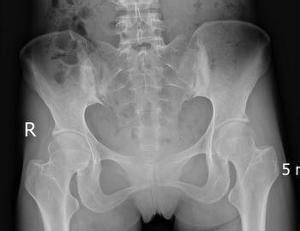

辅助检查:CPR:33.08mg/l,RF:12.30Iu/ml,ESR:55.0mm/h;HLA-B27(+)X光片示:椎体向右侧弯曲,间隙模糊狭窄,骶髂关节炎。

(图:患者骶髂关节X线片)